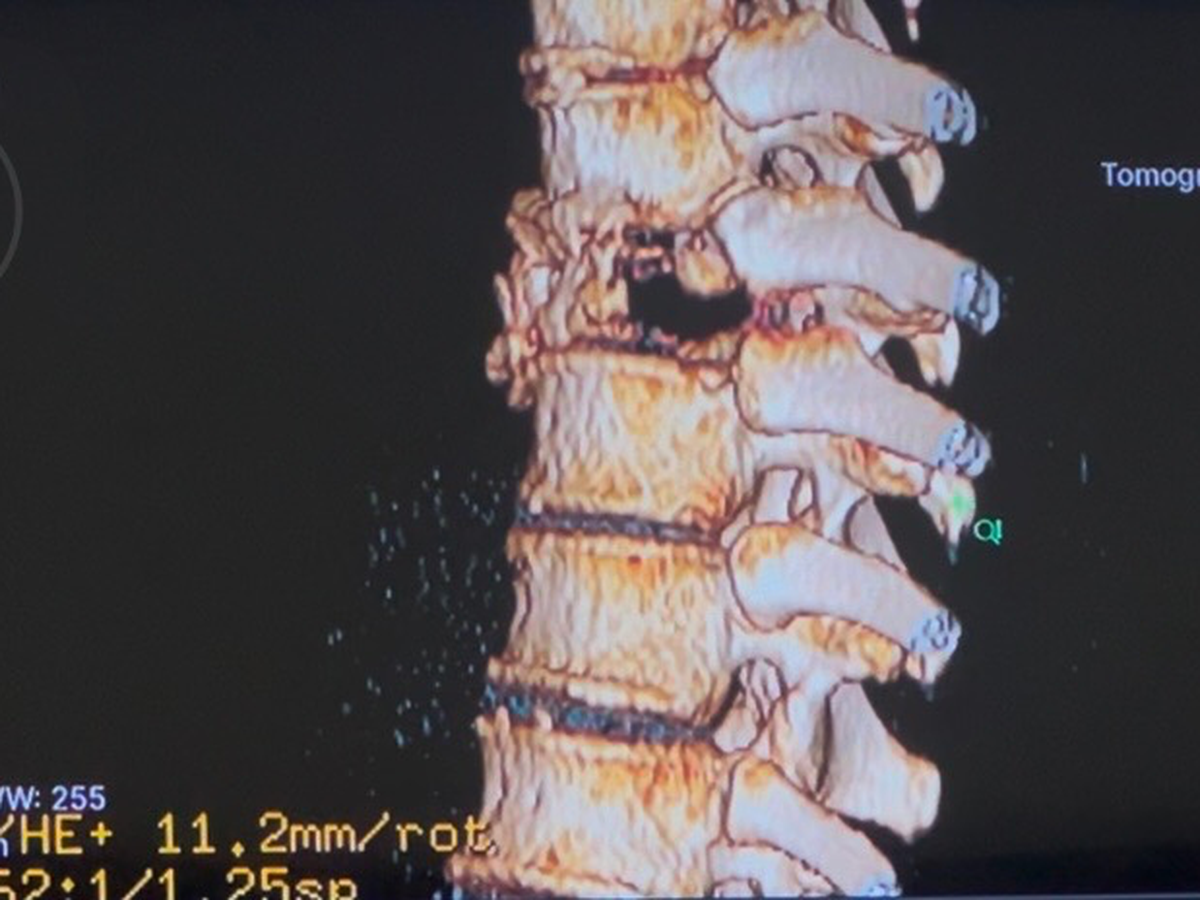

El pasado 31 de mayo de 2025, mientras viajaba en moto con mi padre, fuimos brutalmente atropellados. Yo llevaba casco, iba con precaución… pero la violencia del impacto me cambió la vida en segundos. Desde entonces, vivo con fracturas en mis costillas, una lesión lumbar y una fractura severa en la vértebra T8, que amenaza con dejarme sin movilidad si no recibo atención médica especializada de inmediato.

Diagnóstico actual: Fractura vertebral T8 postraumática con compromiso estructural grave + fracturas costales + protrusión discal lumbar